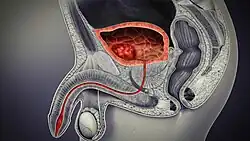

Cancer

Cross-section of the male genitourinary system showing a cancer within the bladder. When a cancer occurs it is most likely to be a transitional cell carcinoma.

Cancer of the bladder is known as bladder cancer. It is usually due to cancer of the urothelium, the cells that line the surface of the bladder. Bladder cancer is more common after the age of 40, and more common in men than women;[33] other risk factors include smoking and exposure to dyes such as aromatic amines and aldehydes.[33] When cancer is present, the most common symptom in an affected person is blood in the urine; a physical medical examination may be otherwise normal, except in late disease.[33] Bladder cancer is most often due to cancer of the cells lining the ureter, called transitional cell carcinoma, although it can more rarely occur as a squamous cell carcinoma if the type of cells lining the urethra have changed due to chronic inflammation, such as due to stones or schistosomiasis.[33]

Investigations performed usually include collecting a sample of urine for an inspection for malignant cells under a microscope, called cytology, as well as medical imaging by a CT urogram or ultrasound.[33] If a concerning lesion is seen, a flexible camera may be inserted into the bladder, called cystoscopy, in order to view the lesion and take a biopsy, and a CT scan will be performed of other body parts (a CT scan of the chest, abdomen and pelvis) to look for additional metastatic lesions.[33]

Treatment depends on the cancer's stage. Cancer present only in the bladder may be removed surgically via cystoscopy; an injection of the chemotherapeutic mitomycin C may be performed at the same time.[33] Cancers that are high grade may be treated with an injection of the BCG vaccine into the bladder wall, and may require surgical removal if it does not resolve.[33] Cancer that is invading through the bladder wall may be managed by complete surgical removal of the bladder (radical cystectomy), with the ureters diverted into a segment of part of ileum connected to a stoma bag on the skin.[33] Prognosis can vary markedly depending on the cancer's stage and grade, with a better prognosis associated with tumours found only in the bladder, that are low grade, that do not invade through the bladder wall, and that is papillary in visual appearance.[33]